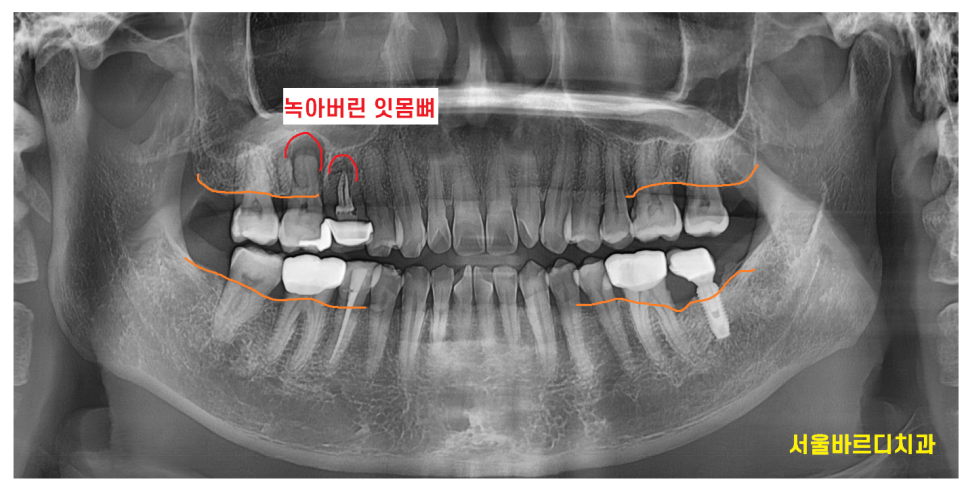

x-ray를 통하여 검사를 해보니

잇몸뼈가 전반적으로 내려가있습니다.

특히나 윗니 양쪽 어금니 부분이 많이 내려가 있으며

230320

오른쪽 윗니 어금니 2개 상태가 많이 안좋습니다.

뿌리쪽에 고름이 있어서

잇몸뼈가 많이 녹았는지 주변보다 까맣게 보입니다.